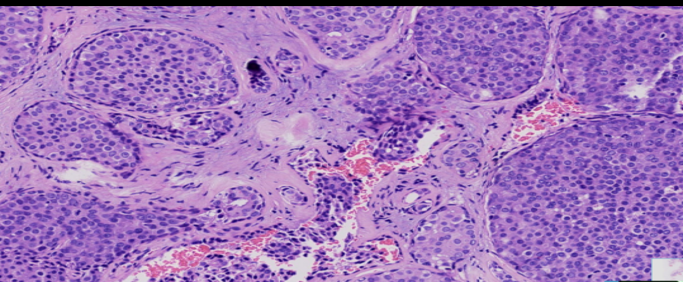

结构特点:轮廓清楚的实性结节纤细的血管轴心。

导管原位癌的分布模式

虽未充满整个管腔,但实性生长。

纤细的脉管轴心

DCIS样,界限清楚、多个、膨胀性结节状

纤细的血管轴心周围细胞呈栅栏状排列

原位癌VS浸润癌

原位SPC:轮廓光滑的圆形结节结节周围无促结缔组织增生结节周围肌上皮可有可无

浸润癌两种浸润方式

1、浸润性实性乳头状癌:保留实性乳头状结构,体积大的团巢,轮廓不规则,间质促纤维反应,肌上皮缺失,原位SPC背景

2、实性乳头状癌伴浸润:轮廓圆滑的结节,伴有浸润性成分,包括粘液癌,NET,浸润性癌(NST)